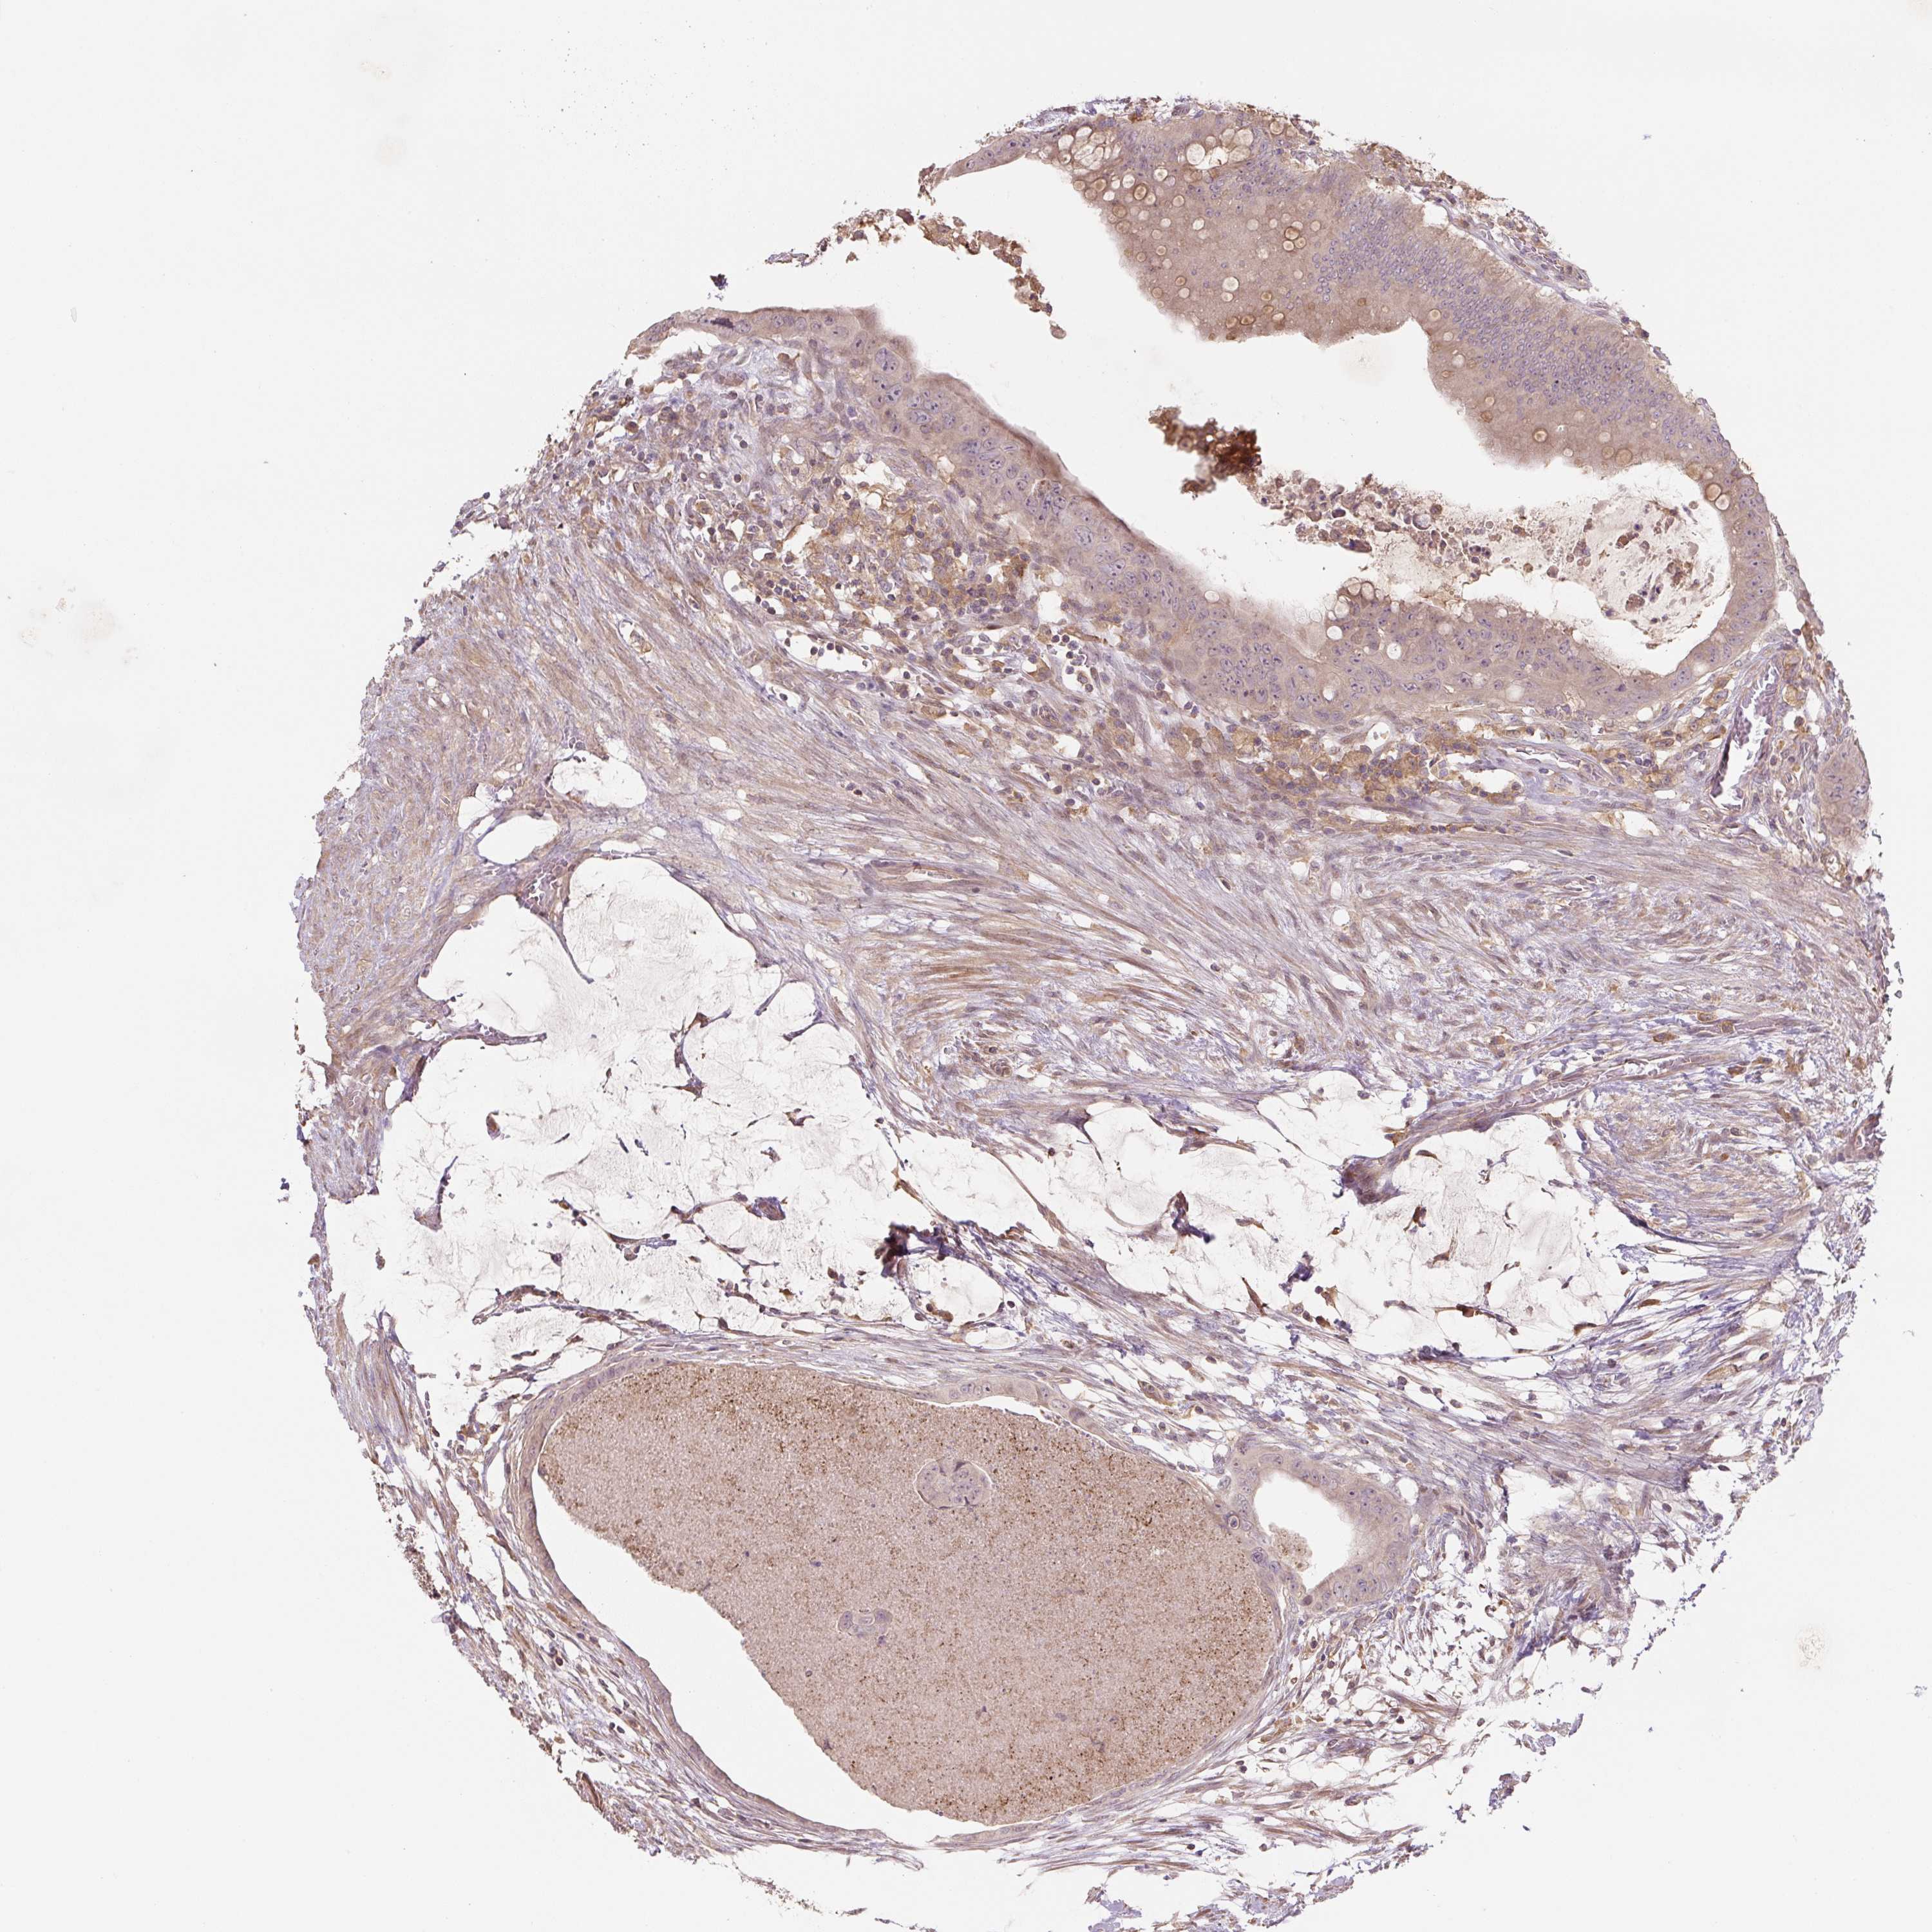

Colorectal cancer

Human cancer

Colon adenocarcinoma